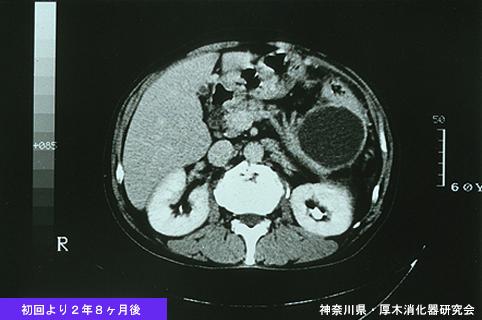

症例提示(所在地,施設名等): 神奈川県・ 厚木消化器研究会

症例登録日 2004/02/12

性別 男性

年齢 55-59

取得年代 1990-1994

疾患(病理主体)の分類腫瘍様病変/近接臓器からの浸潤

部位(臓器別)大腸/下行

検査方法CT

病変の最大径(ミリ)40以上